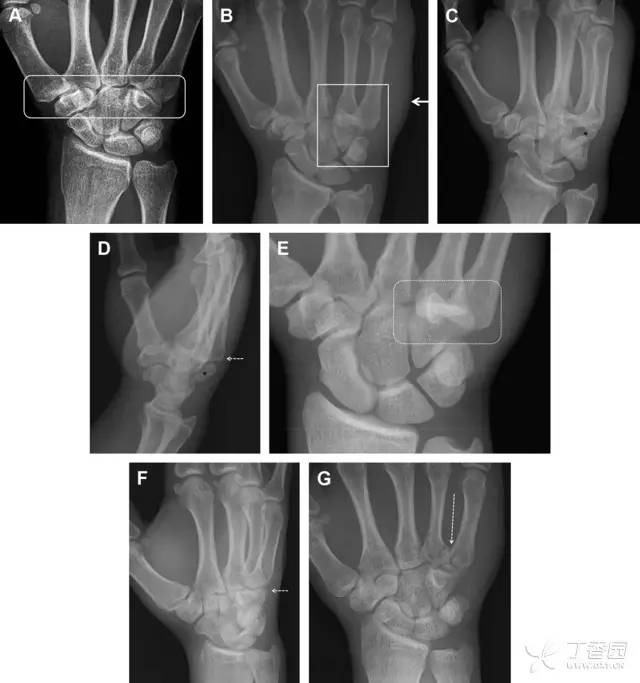

32 掌板骨折

掌板是掌指关节和指间关节关节囊掌侧的纤维结构,防止关节过伸。掌板的远端部是增厚的纤维软骨,附着于指骨掌侧基底部,而其两侧与侧副韧带的纤维融合。掌板骨折多发生于过伸损伤,为撕脱性骨折。

图 3 掌板骨折(A~C)小指前后位、斜位、侧位片,由于骨折的部位及特点,在前后位片上通常难以发现骨折;放大后的斜位(D)、侧位(E)可见一骨碎片(白色箭头)

33 腕掌关节骨折脱位

腕掌关节骨折脱位为高能量损伤,常伴有神经损伤。腕掌关节组成骨多,侧位片上重叠遮挡多,骨折不易发现,容易漏诊。在前后位片上,关节面不平滑、关节间隙不对称、关节皮质破坏、关节面重叠常提示腕掌关节骨折脱位。特别是第 4、5 腕掌关节脱位,在前后位片上不容易发现;该损伤不稳定,也称为「变异型拳击手损伤/骨折」。

图 4 第 4、5 腕掌关节骨折脱位。(A)正常腕掌关节,关节面平衡起伏、平行;前后位(B)、斜位(C)、侧位(D),第 5 掌骨近端附近软组织肿胀(白色箭头),冠状面关节面重叠,背侧撞击剪切应力致钩状骨骨折(*),在前后位及斜位片上可见双密度影。第 4 掌骨底部可见微小骨折碎片(D,虚线箭头),第 4、5 掌骨掌侧成角。(E~G)变异型拳击手损伤:第 4、5 掌骨背侧脱位而未见骨折(E,虚线方框),钩状骨有骨折小碎片(F,短虚线箭头),第 4 掌骨基底部关节内骨折(G,长虚线箭头)

34 钩状骨骨折

钩状骨骨折可发生于体部和钩部,钩部骨折更多见,可合并有第 4、5 腕掌关节脱位。受伤机制由直接*力暴**或腕横韧带撕脱伤所致。骨折征象包括钩部无显示、骨皮质边缘模糊、硬化或双密度影等。常规的正侧位常无法明确诊断,需要加拍腕管位,可清晰显示其钩部。

图 5 打高尔夫球后腕部急性疼痛。常规腕关节 X 线片正常(X)。腕管位片(B)隐约可见钩部横行骨折(虚线箭头),CT 检查(C、D)进一步明确了诊断